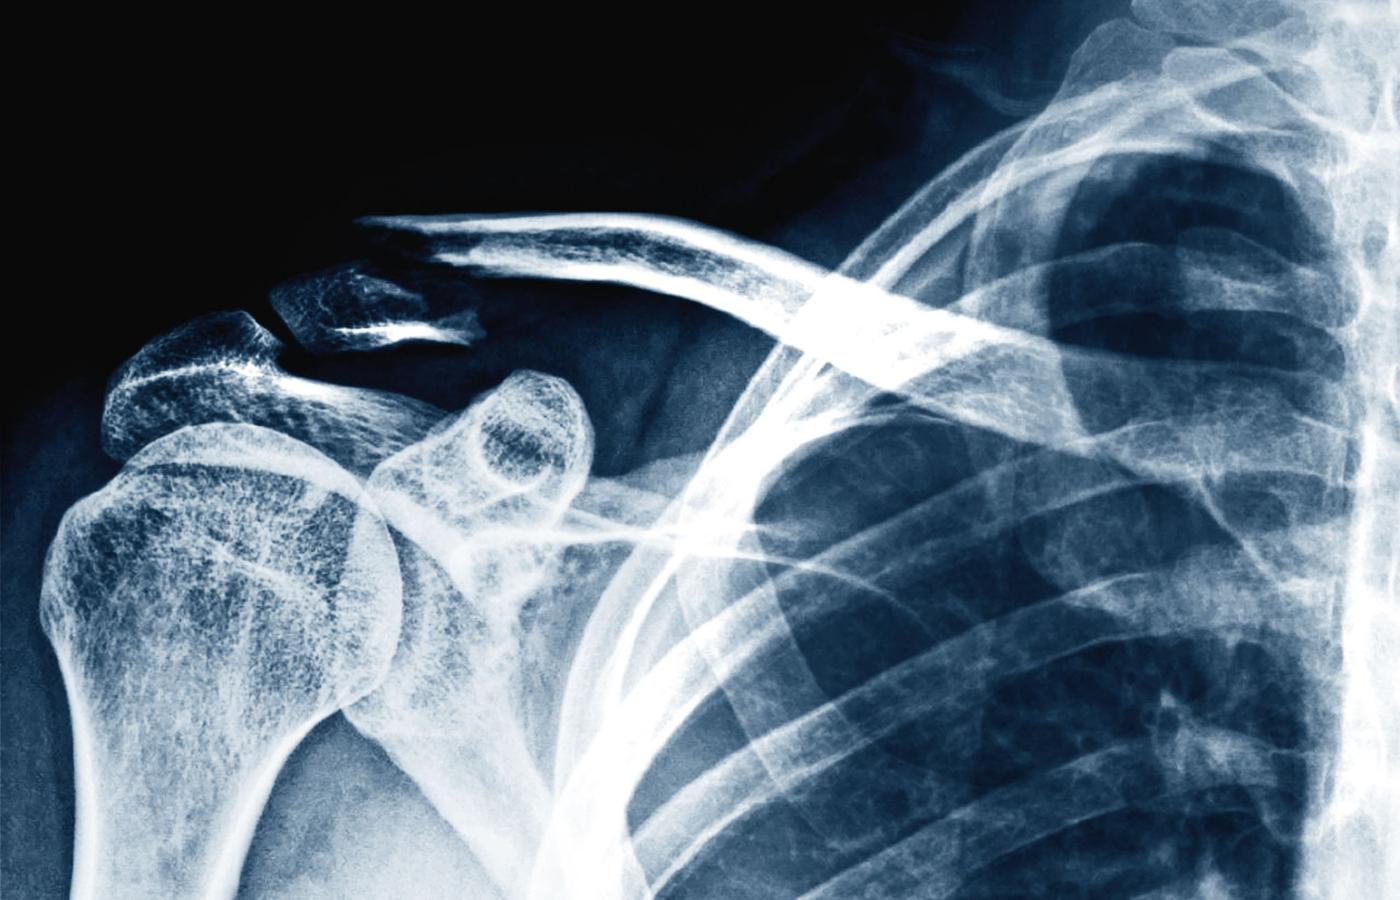

Złamanie kości obojczyka. Złamanie kości obojczyka. materiały prasowe